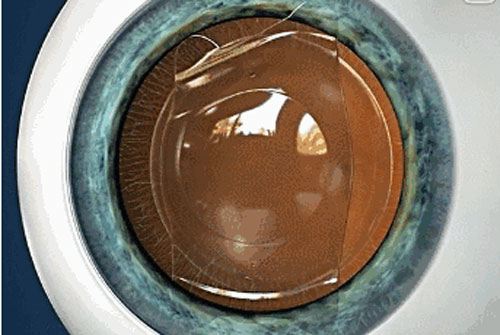

全飛秒治療近視屬于激光治療近視手術(shù)的一種手術(shù)方式,而激光治療近視手術(shù)自90年代進(jìn)入中國以來,經(jīng)歷了30年的發(fā)展,早已從大家不知發(fā)展到近視眼都知曉的一種快速提升裸眼視力的方法。如今,近視手術(shù)已經(jīng)發(fā)展到微創(chuàng)全飛秒時(shí)代,個(gè)性化飛秒激光不需要制作角膜瓣,僅在角膜上方制作2毫米的切口,取出飛秒激光制作的透鏡組織,即可矯正近視。全飛秒激光全程使用飛秒激光完成,保留了角膜表面的完整性,減少對(duì)角膜神經(jīng)纖維的損傷,術(shù)后抗撞擊能力強(qiáng),長期不怕外傷,第二天即可正常生活,運(yùn)動(dòng)不受限制,特別適合術(shù)后要參加長期高強(qiáng)度對(duì)抗訓(xùn)練的軍人、警察和運(yùn)動(dòng)員。